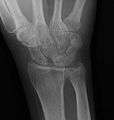

Stress view showing scapholunate instability